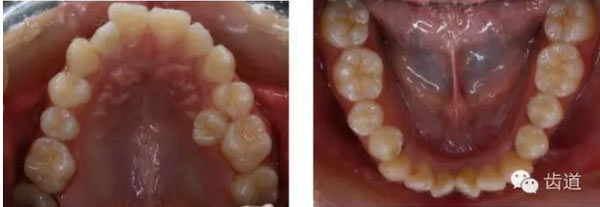

上牙弓:尖圓形,25腭側(cè)完全錯(cuò)位,26前移

治療后模型

橫向不調(diào):牙弓寬度輕度不調(diào)的解決在于上頜適當(dāng)?shù)臄U(kuò)弓與后退左上牙列,以及下頜適當(dāng)?shù)目s弓與下磨牙前移,矯治后上頜磨牙寬度由41.8mm變?yōu)?3.1mm,下頜磨牙寬度由39.6mm變?yōu)?7.8mm。